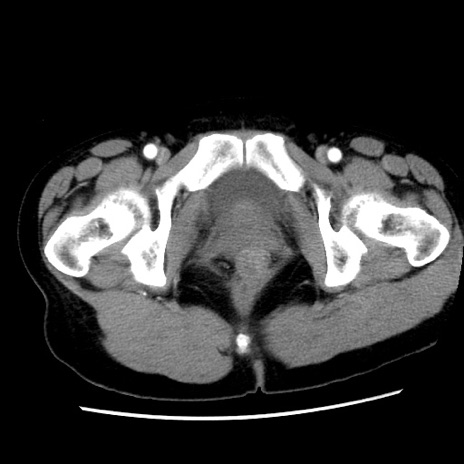

症例10(横断像)

【症例】 50歳代女性

【主訴】 腹痛

【現病歴】前日生レバーを食べた。今朝に排便あり。 昼前に突然発症の腹痛を生じ、当院救急外来を受診した。

【既往歴】 子宮筋腫にてで子宮全摘後

【身体所見】 意識清明、腹部:平坦、軟、下腹部やや左を中心に圧痛・反跳痛あり、筋性防御あり

【データ】WBC 7800、CRP 0.07